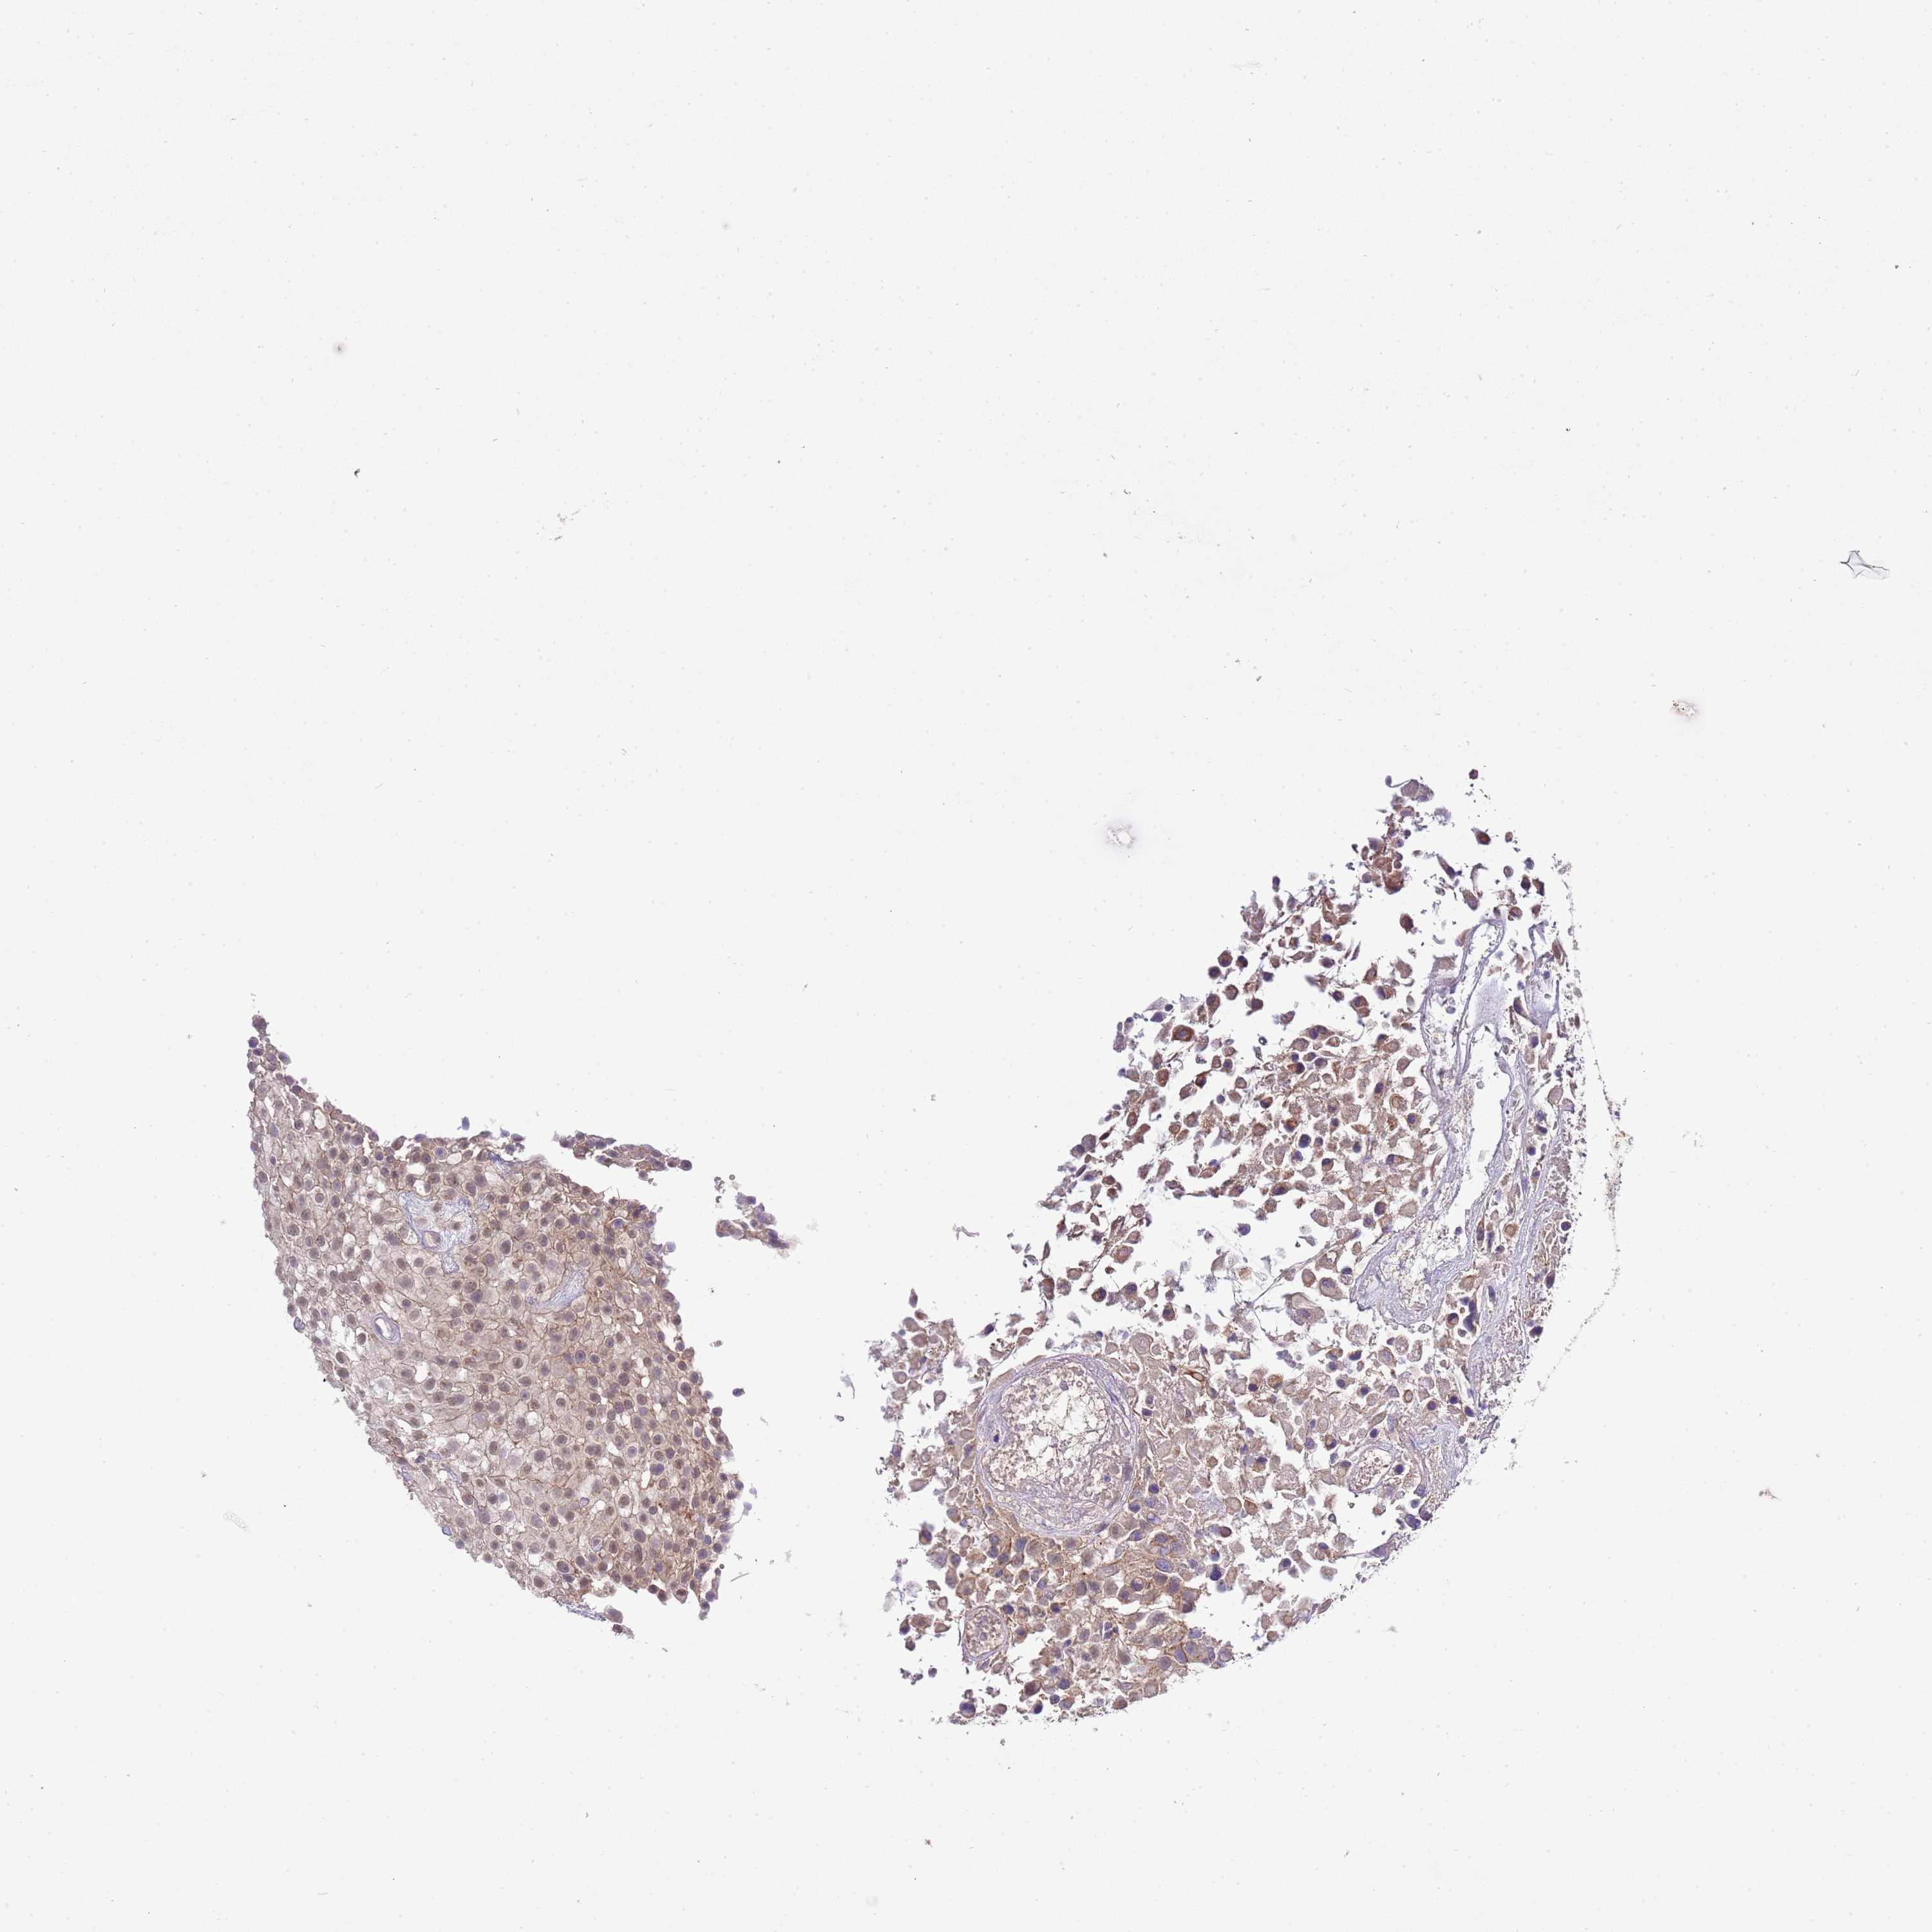

UROTHELIAL CANCER - Protein expressioni

A mouse-over function shows sample information and annotation data. Click on an image to view it in a full screen mode. Samples can be filtered based on level of antibody staining by selecting one or several of the following categories: high, medium, low and not detected. The assay and annotation is described here.

Note that samples used for immunohistochemistry by the Human Protein Atlas do not correspond to samples in the TCGA dataset.

Antibody stainingi

Antibody staining in the annotated cell types in the current human tissue is reported as not detected, low, medium, or high, based on conventional immunohistochemistry profiling in selected tissues. This score is based on the combination of the staining intensity and fraction of stained cells.

Each image is clickable and will lead to virtual microscopy that enables deeper exploration of all samples and also displays staining intensity scores, fraction scores and subcellular localization as well as patient and tissue information for each sample.

Antibody HPA049331

Antibody HPA056959

Urothelial carcinoma, Low grade

Urothelial carcinoma, High grade

Urothelial carcinoma, NOS